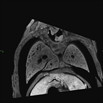

| Serial micro-MRI image stack of 2459-007-NA in the coronal plane reveals DORV and subaortic VSD

Click thumbnail to play movie. | b2b2459Clo/b2b2459Clo | C57BL/6J-b2b2459Clo |